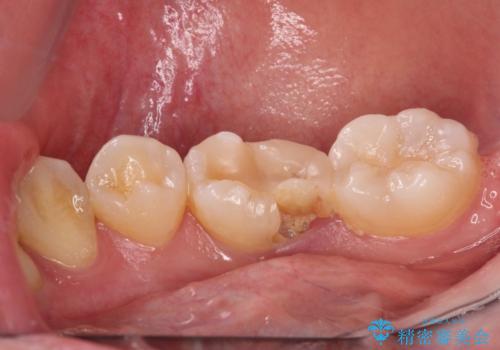

- 奥歯が食事中に歯が欠けて、しみて痛いとのことで来院された患者様です。

レントゲン写真からも、舌側に大きな虫歯があることが分かりました。

症状から神経を取り除く可能性も考慮し、オールセラミッククラウンにて補綴治療することとしました。